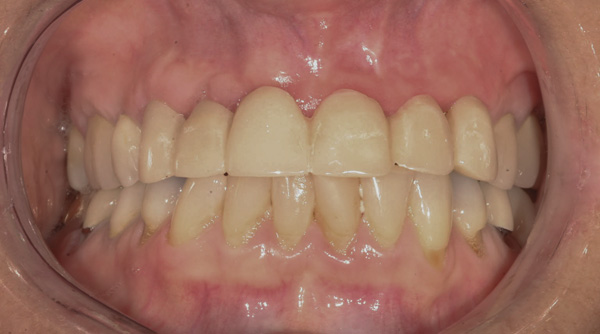

Case 5 – Conical Abutments Used As Temporary Abutments

Background: The patient in this case presented with a failing dentition due to generalized severe periodontal disease with secondary endodontic lesions. She adamantly refused to wear removable transitional prostheses. Full maxillary and mandibular extractions were performed in the first phase of treatment. Not all implants could be placed in this initial phase due to the need for healing of certain grafted sites. The implants placed in this first phase were loaded with conical abutments and, in some cases, their angulated counterparts (Figure 16 and Figure 17). These stock titanium abutments were selected to avoid the need, as in Case 3, to change or remill the more costly custom abutments. They also have the advantage of making it unnecessary to use temporary cement near and around surgical sites, as they use occlusal screws only for retention.

Results: Stock titanium abutments were used until all tissue healing was achieved and the secondary implants had healed. Figure 18 shows the maxillary and mandibular custom abutments inserted. Figure 19 shows a close-up of the patient’s right side quadrants, depicting the final case 15 months after initial treatment began. Recession can be seen around units corresponding to teeth Nos. 5 and 6. In this case, the authors attempted to minimize recession susceptibility by employing stock temporary screw-retained abutments during healing phases throughout the initial stages of the treatment plan. Despite these efforts, recession still occurred in certain areas where the implants were labially placed. Since the photographs shown in this case were taken, an unsuccessful attempt was made by the patient’s surgeon to graft soft tissue around these sites with recession.

Quantity of buccal bone—Le and Borzabadi-Farahani concluded that a minimum of 2 mm of facial bone is necessary to prevent future recession.23 Bashutski and Wang noted that the most common esthetic complication is gingival recession, and cited inadequate buccal bone thickness, implants placed too far buccally, and failure to graft “jumping distance” during immediate placement in the etiology of recession.22 Case 5’s final result (Figure 19) shows more than 2 mm of labial recession around the implant-supported abutments at sites Nos. 5 and 6 (this was also the case at sites Nos. 13 and 14). Referring back to Figure 17, it is apparent that sites Nos. 5, 6, 8, and 12 demonstrate very little buccal soft tissue due to the labial placement of the implants. Butler and Kinzer support the premise that there must be adequate bone volume facially, even when the implant is placed ideally, and they found that many complications are related more to the implant position and the associated anatomical findings.21

Buccal-labial position of implants—Saadoun and Touati concluded that the buccal orientation of the implant will impinge upon the buccal cortical wall and induce bone resorption and apical migration of the tissue.13 Chu et al reported that if the implant is not placed more palatally and 3-mm to 4-mm apical to the free gingival margin to assure the proper emergence profile, the esthetic outcome may be compromised.34 Bengazi et al’s 2-year longitudinal study demonstrated that anteriorly positioned implants demonstrated slightly more recession than implants in posterior positions.17 Buccal implant placement can be clearly seen in Case 5 (Figure 17) with healing abutments in place.

Proximity to adjacent implants—Tarnow et al24 and Tarnow et al25 recommend that a minimum of 3 mm of bone exist between two adjacent implants. In sites Nos. 13 and 14 (Case 5) the fixture heads have less than 2 mm between them, and the abutments have less than 1 mm (Figure 17). Because interdental tissues do not have the same level of support between implants as they do with natural teeth, interdental distance becomes more critical in predicting the final soft-tissue position.

Figure 16 First-phase implants loaded with conical abutments and, in some cases, their angulated counterparts.

Figure 16

Figure 17 First-phase implants loaded with conical abutments and, in some cases, their angulated counterparts.

Figure 17

Figure 18 Custom abutments inserted.

Figure 18

Figure 19 Final result 15 months after initial treatment began, showing patient’s right side quadrants.

Figure 19